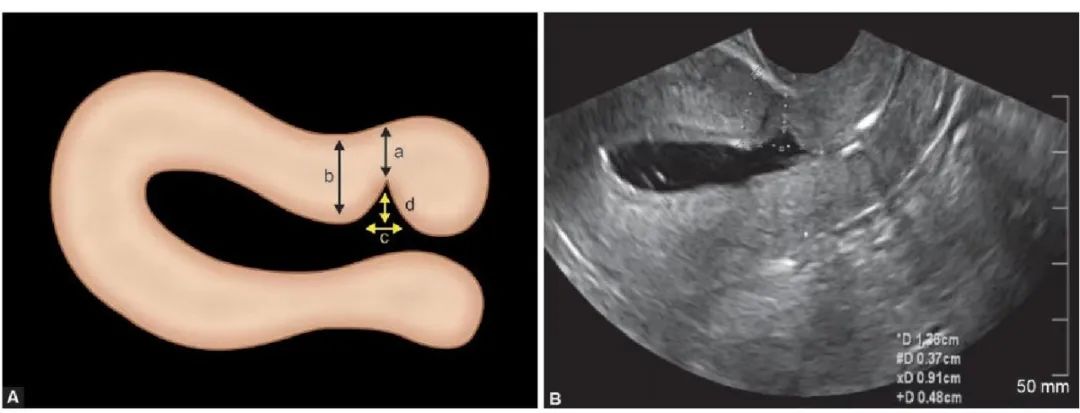

对于手术,我们老百姓有个俗称,叫「开刀」。既然是开刀自然会有一个切口,当剖宫产术后的子宫切口愈合缺陷时,切口处会出现一个与宫腔相通的凹陷,看起来好像一道沟,这个凹陷就是我们所说的憩室。

剖宫产术后子宫切口憩室 (previous cesareanscar defect,PCSD )以往报道较少 ,1955 年西班牙学者首次报道了子宫切口憩室。由于它是在剖宫产后出现,所以被称为剖宫产术后子宫切口憩室,又俗称为剖宫产瘢痕憩室。

子宫切口憩室多位于子宫下段或峡部,少数位于宫颈上段,主要与原剖宫产切口部位及剖宫产时临床宫颈有无缩短或扩展有关,简单点说,它就像一间违章改建的“危房”。